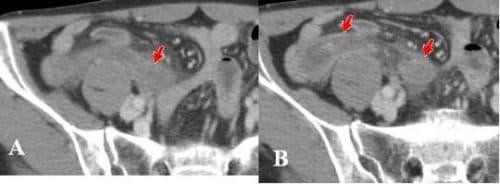

Ca 2: Bệnh nhân 68 tuổi, nữ giới đau hố chậu phải ngày 2

Ruột thừa to, thành bắt thuốc cản quang mạnh, trong lòng chứa dịch

Hình 2A: A, Hình ảnh ruột thừa to, thành bắt thuốc cản quang mạnh, trong lòng chứa dịch (mũi tên đỏ). B, Thâm nhiễm mỡ mạc treo xung quanh (mũi tên xanh).

Ruột thừa viêm mủ có giả mạc

Hình 2B: A, tái tạo coronal, B sagittal thấy rõ hình ảnh ruột thừa thành bắt thuốc cản quang mạnh, trong lòng chứa dịch (mũi tên đỏ), thâm nhiễm mỡ xung quanh.

Tình trạng: Ruột thừa viêm mủ có giả mạc